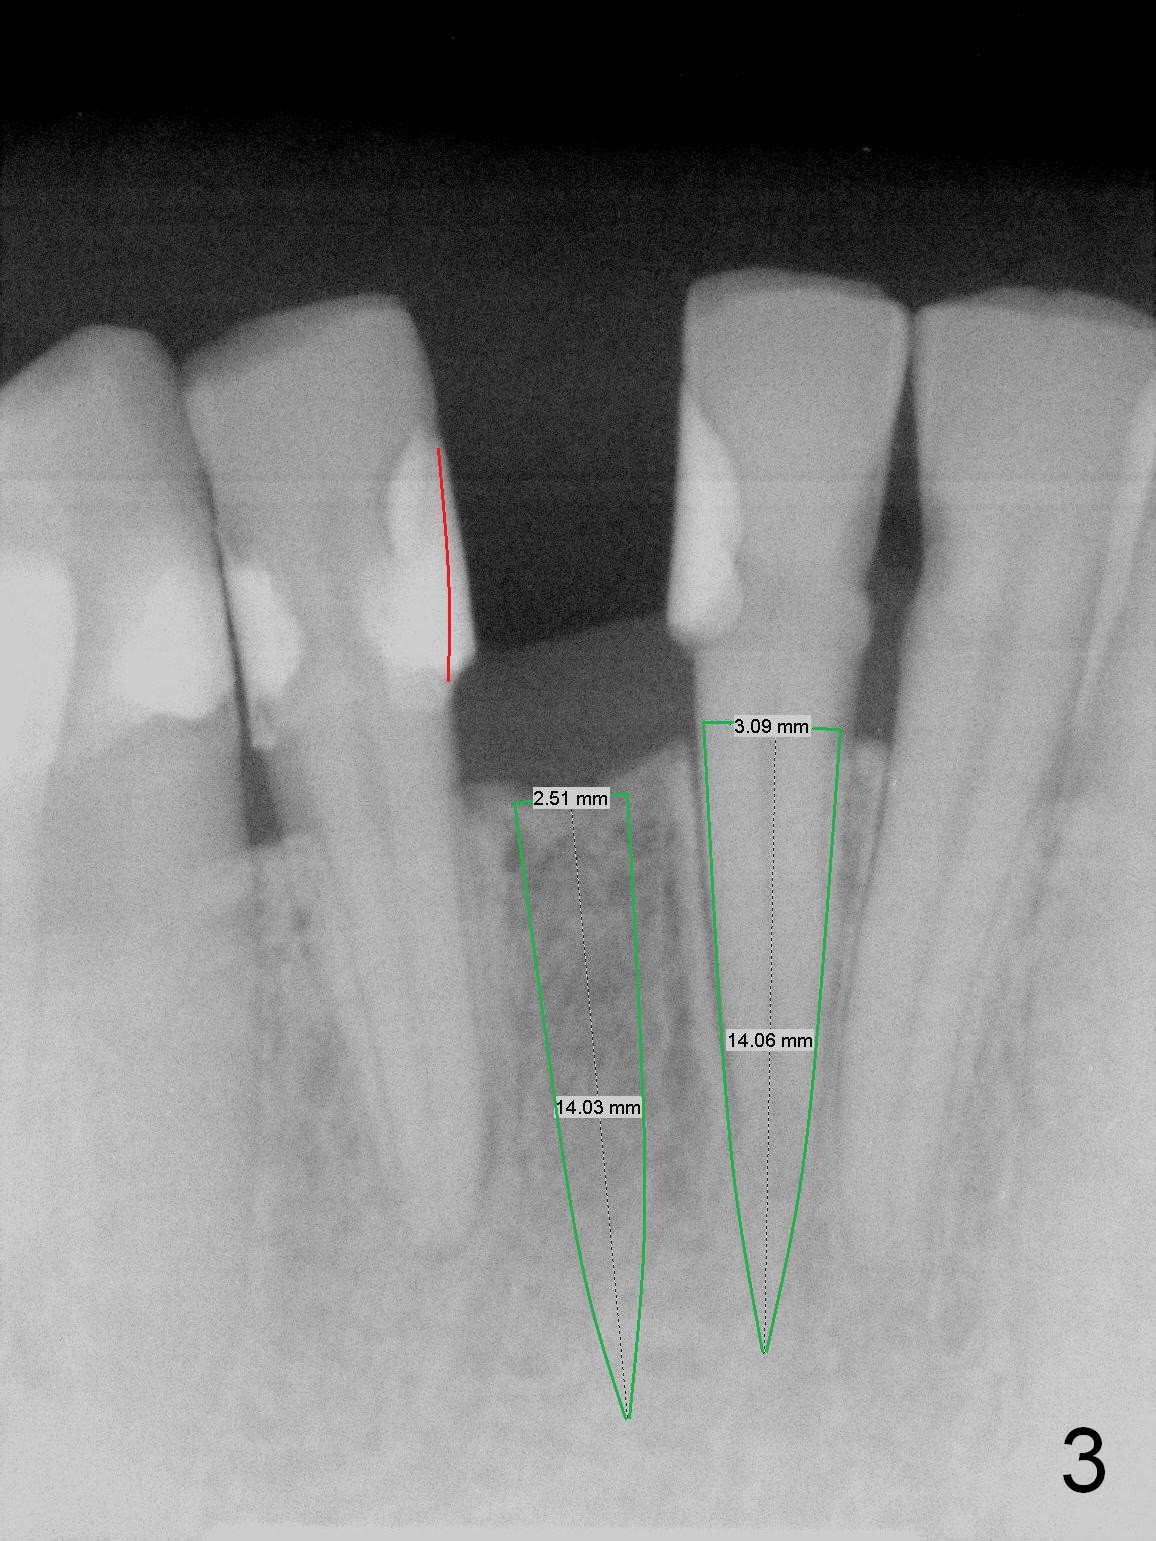

A 3 or 3.5 mm 1-piece implant is placed at #24 (Fig.3) after Metronidazole socket soaking. The larger one is chosen (3.5 mm (Tatum)) if the implant at #25 fails to be placed. A dummy implant is placed partially to test trajectory. If the latter is bad, use an angled 1-piece one (Tatum). The composite overhang (Fig.2 *) is to be trimmed (Fig.3 red line). Take preop photos to show the concave buccal plate (Fig.4a) and intra- and post-op ones to show bone expansion (Fig.4b-d).